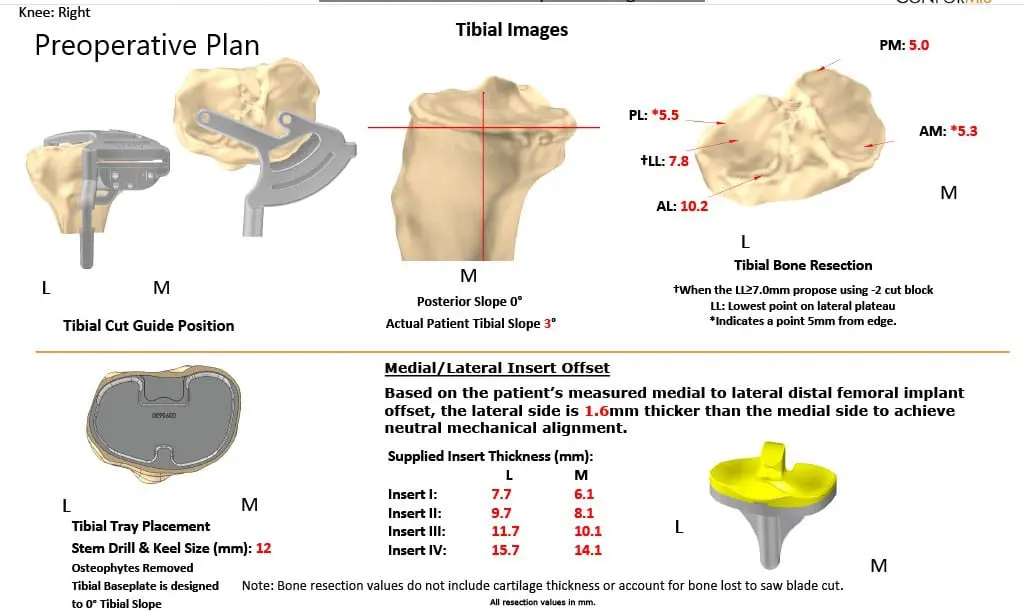

As a part of the preparation of the custom implants, a preoperative CT was obtained a few weeks prior to surgery. The results were utilized to create 3D images of the patient’s unique anatomy. Customized implants were then made along with disposable custom instruments. A preoperative plan was formalized to aid the surgery in precision cuts and alignment.

Complete Orthopedics patient-specific surgical plan for a right custom knee replacement in a 59-year-old male.